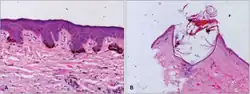

Diagnosis

Skin biopsy